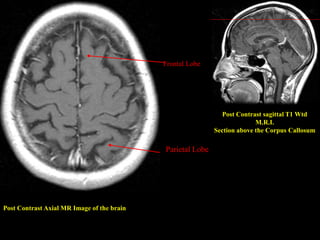

Post Contrast Axial MR Image of the brain

Post Contrast sagittal T1 Wtd

M.R.I.

Section above the Corpus Callosum

Parietal Lobe

Frontal Lobe